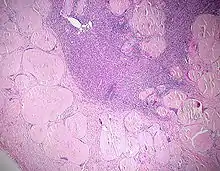

LANGHANS-Riesenzellen in einem Tbc-Granulom, transbronchiale Biopsie

• Käsige Nekrose - Bsp.: Tbc (Epitheloidzelliges Granulom mit Langhans-Riesenzellen und zentraler käsiger Nekrose)